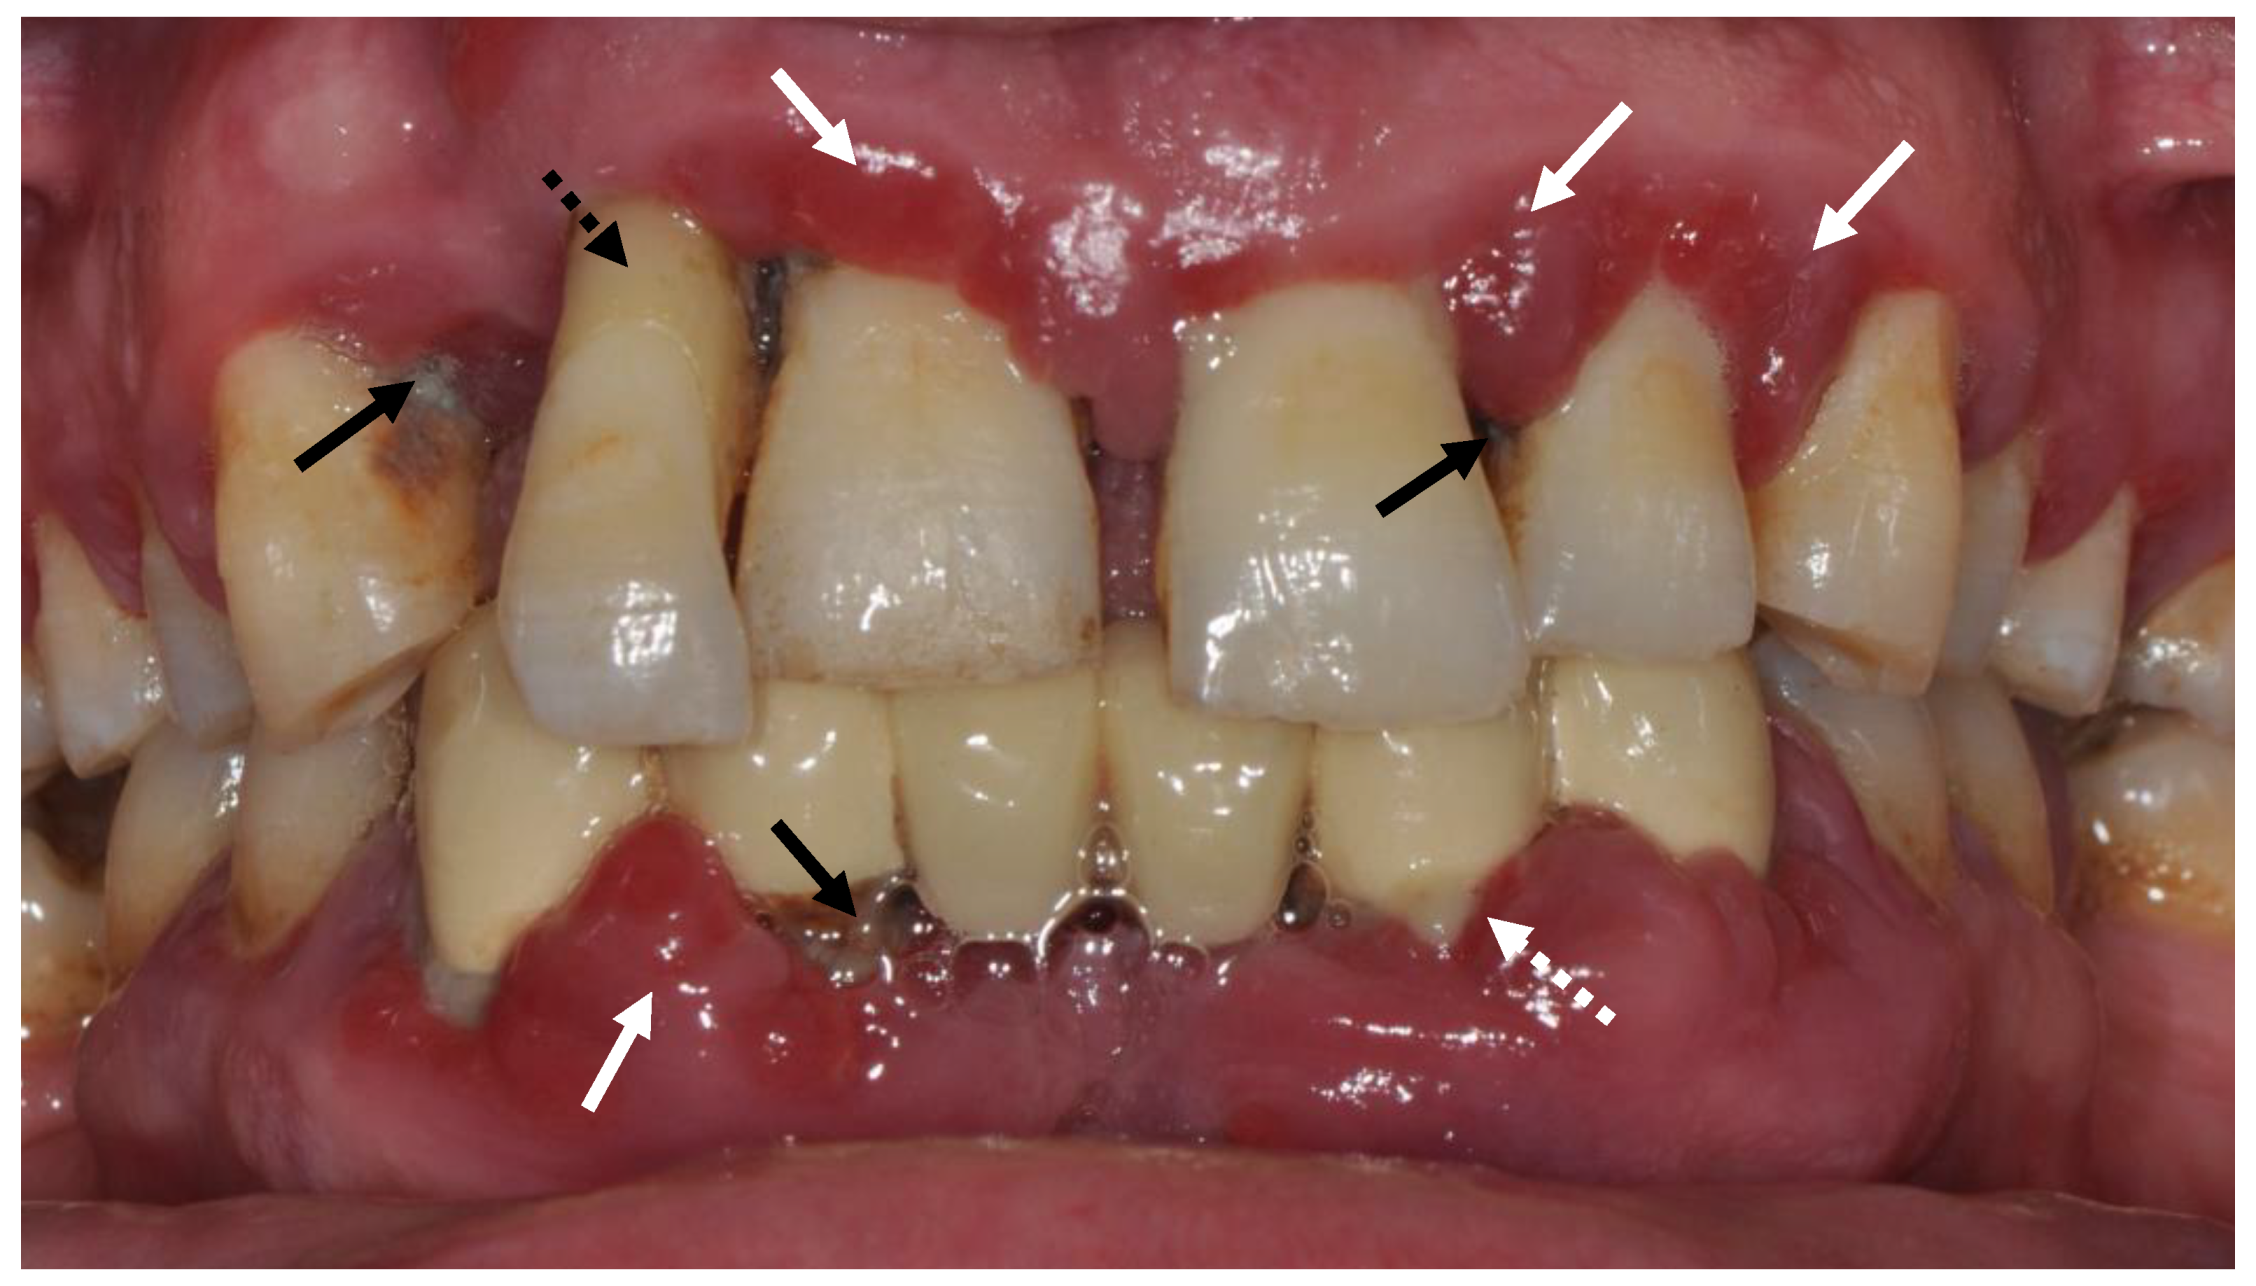

:1. Periodontal Health and Disease